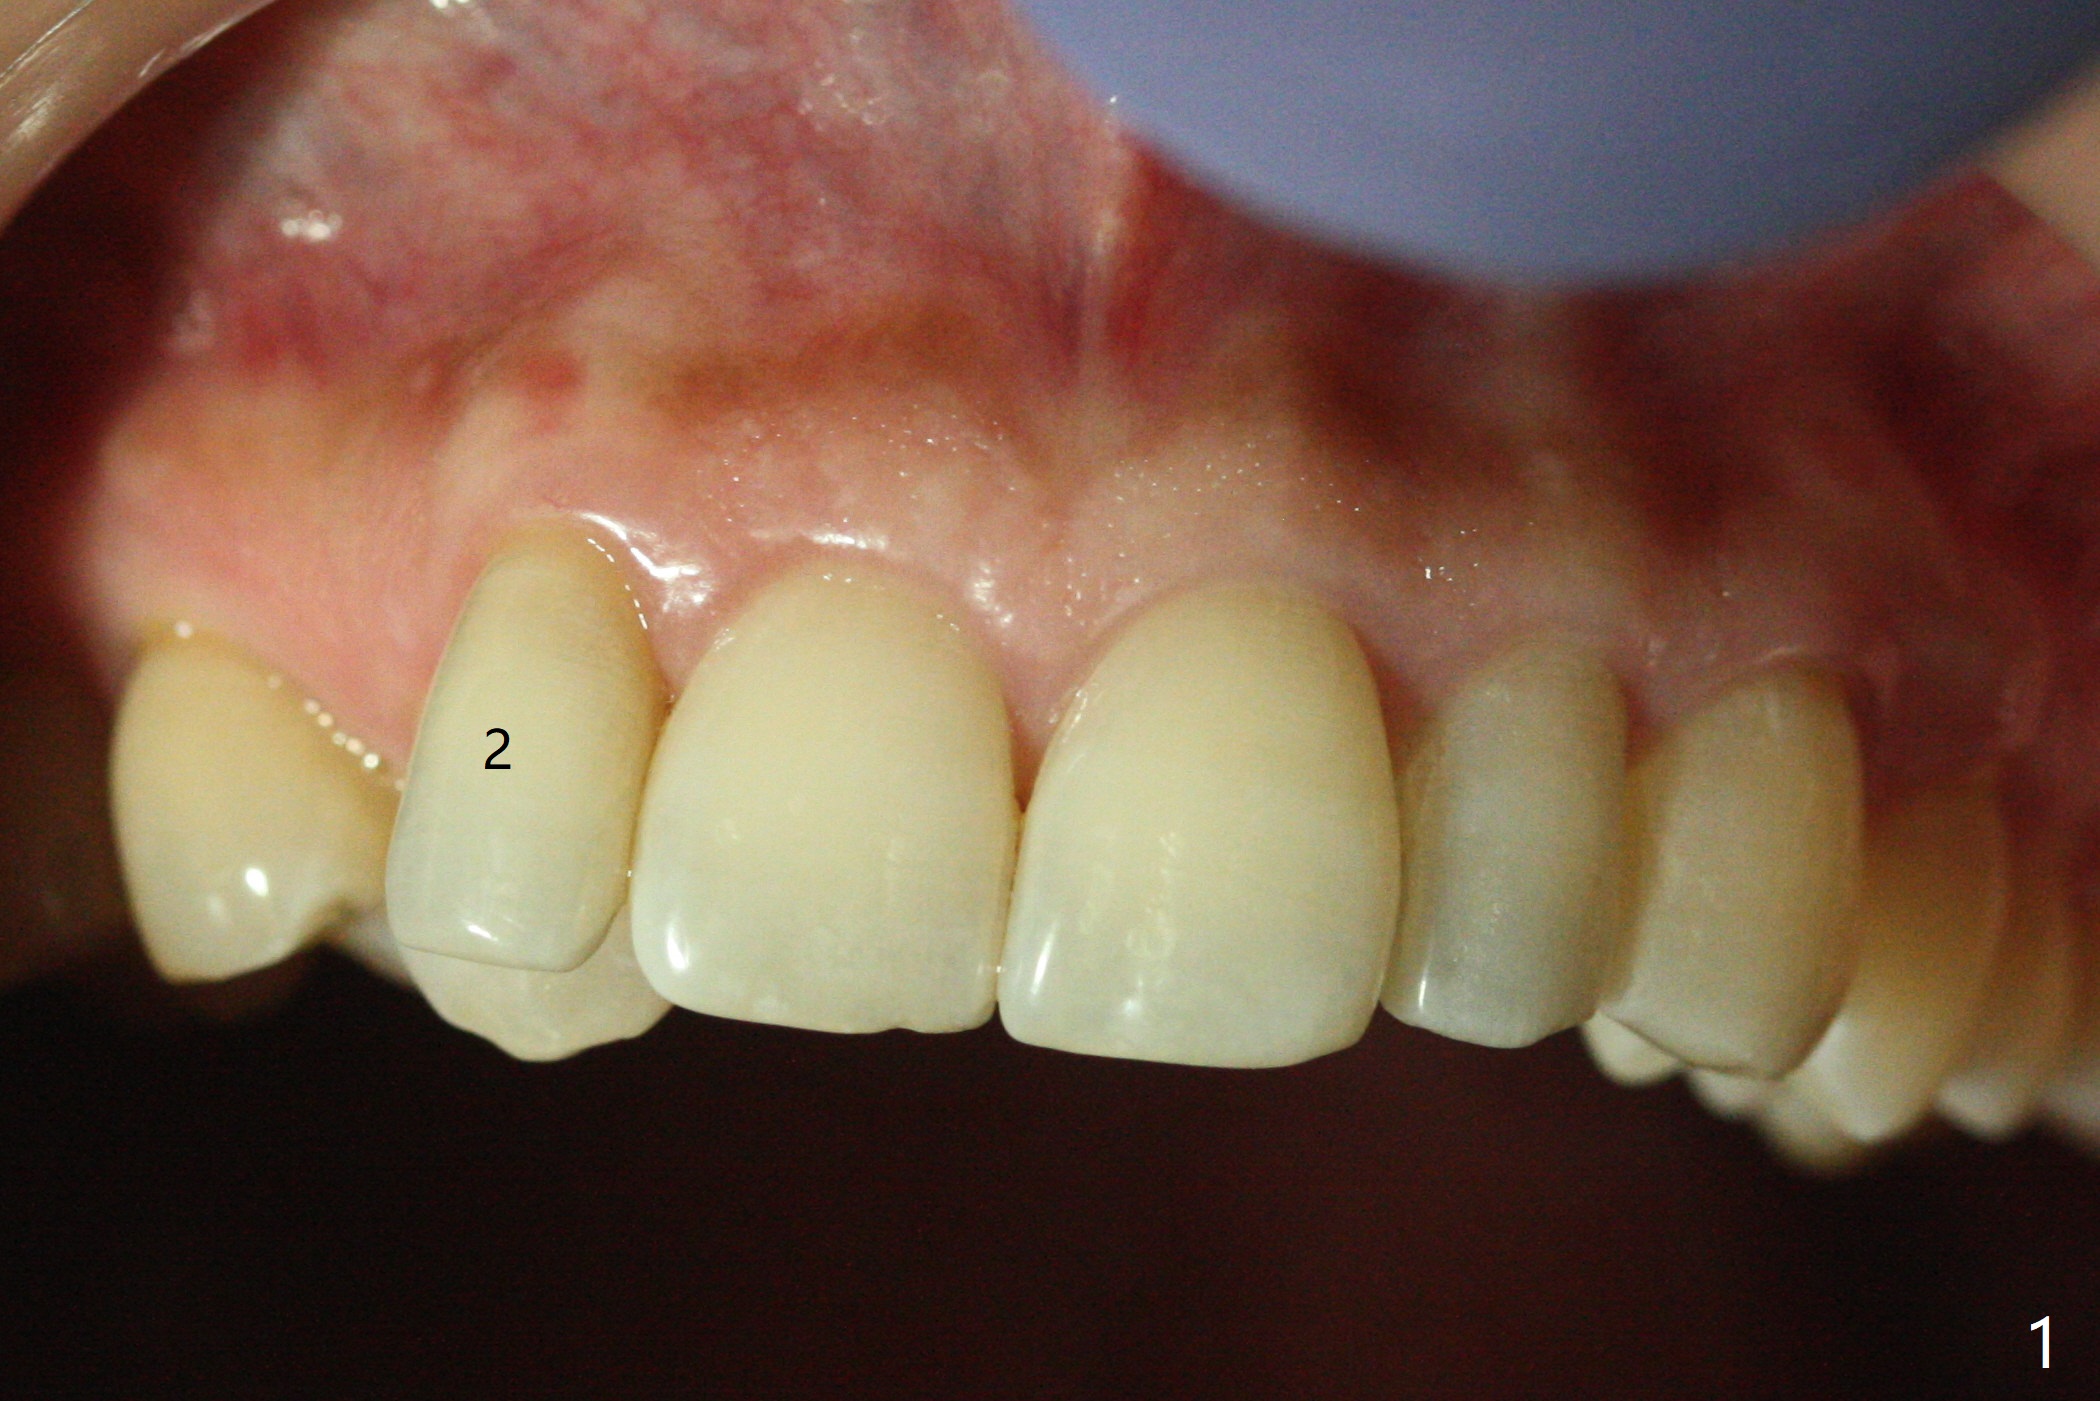

A 54-year-old woman seeks treatment for the tender upper right lateral incisor (Fig.1-4: 2 because of palatal cervical caries (Fig.3 <) and periapical radiolucency (*)), which overlaps with the palatal canine (3). One of treatment options is to extract the lateral and to orthodontically move the canine to the position of the lateral, particularly the root (Fig.5 arrow). When the lateral is removed, the labial bone of the canine is thin (Fig.6). Allograft is placed (Fig.8 * and dashed line), covered with Amnion-Chorion Allograft (Bioxclude) and sutured with 4-0 PGA (Fig.7). The wound heals 9 days postop (Fig.9,10). The patient is grateful because of no pain, which she thinks is due to bone graft, whereas Amnion-Chorion membrane is another contributory factor. The lateral root convexity remains 1 month postop (Fig.11 *); she is undecided upon orthodontic treatment.